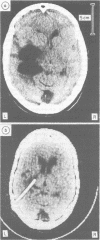

Three cases of a form of focal hydrocephalus are described which the authors term "entrapment of the temporal horn". Obstruction of one lateral ventricle in the region of the trigone isolates the temporal horn. Continued secretion of cerebrospinal fluid within the temporal horn causes it to behave as a mass lesion. In the cases described the causes of the condition were recurrent glioma, previous tuberculous meningitis and surgical excision of an arteriovenous malformation which extended into the trigone. Shunting of the trapped temporal horn provides satisfactory treatment.